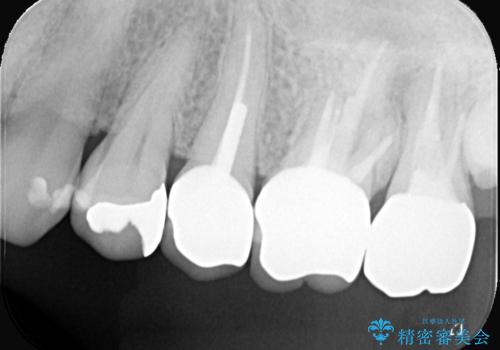

- 主訴:いつも物が詰まる場所があり気になる。衛生士に被せものと土台の境目に汚れが溜まっている箇所があると指摘され気になっている。

過去に入れた被せものと土台の歯との適合が悪く、隙間が出来ておりそこに汚れが溜まりやすい状態になっていました。セラミッククラウンでのやり替えとなりました。

唇側マージン不適なこと説明し、審美性・適合性に優れたセラミッククラウン(スタンダード)でのやり替えとなりました。

治療途中、一度仮歯に置き換えを行っています。